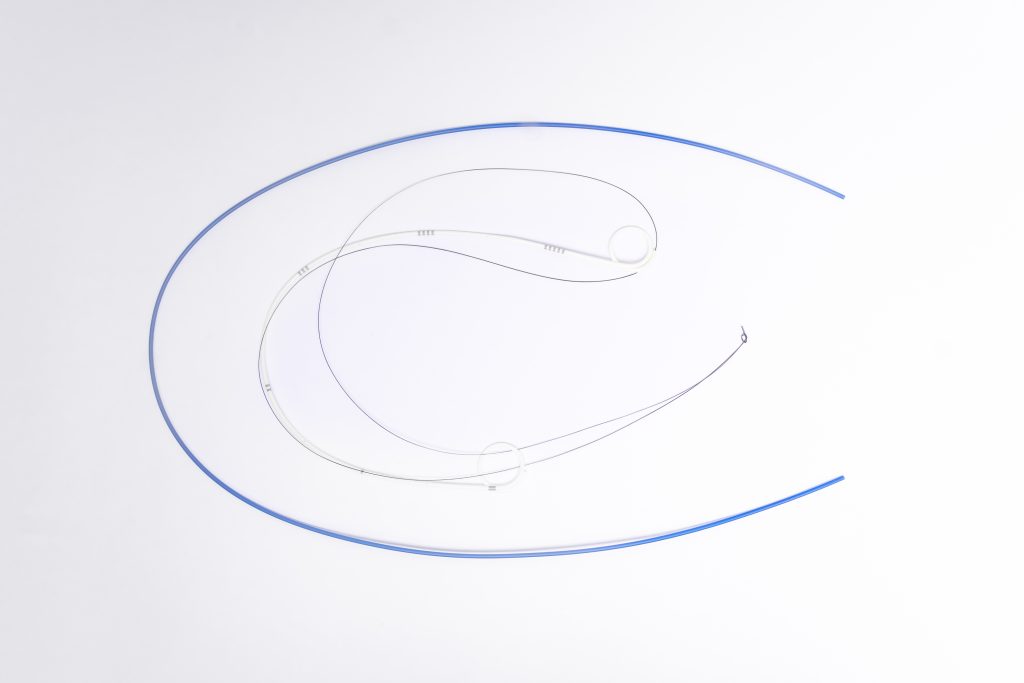

ARIA Wire Rapid Guid – Fio Guia Hidrofílico

Fio Guia Hidrofílico

O fio guia hidrofílico possui revestimento especial que reduz o atrito, proporcionando passagem suave mesmo em trajetos tortuosos ou estreitos. Ideal para acessos difíceis e manipulação atraumática.